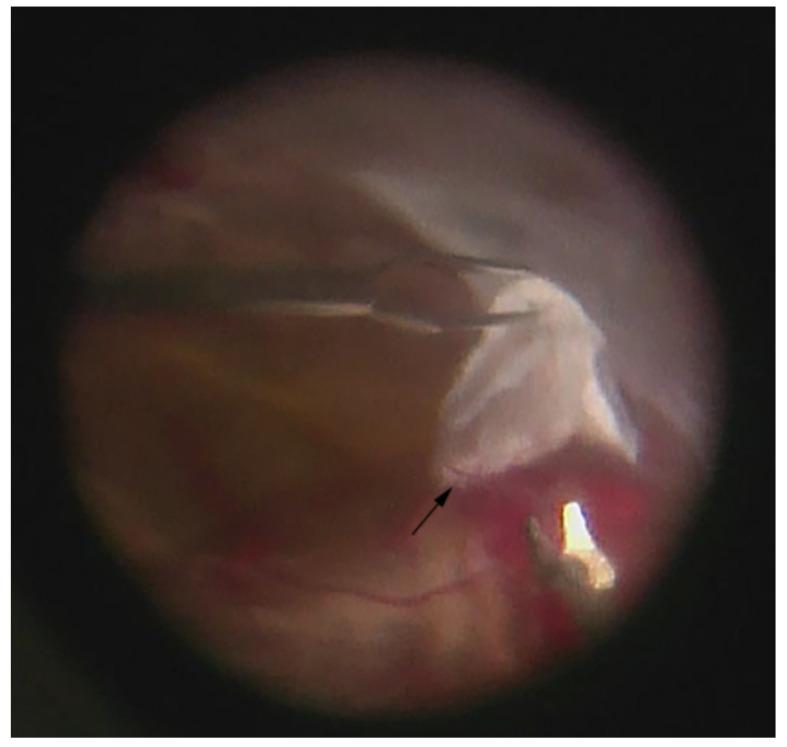

The Vitreous Ecosystem in Diabetic Retinopathy: Insight into the Patho-Mechanisms of Disease.

Diabetic retinopathy is one of the leading causes of blindness in the world with the incidence of disease ever-increasing worldwide. The vitreous humor represents an extensive and complex interactive arena for cytokines in the diabetic eye. In recent decades, there has been significant progress in understanding this environment and its implications in disease pathophysiology. In this review, we investigate the vitreous ecosystem in diabetic retinopathy at the molecular level. Areas of concentration include: the current level of knowledge of growth factors, cytokine and chemokine mediators, and lipid-derived metabolites in the vitreous. We discuss the molecular patho-mechanisms of diabetic retinopathy based upon current vitreous research.